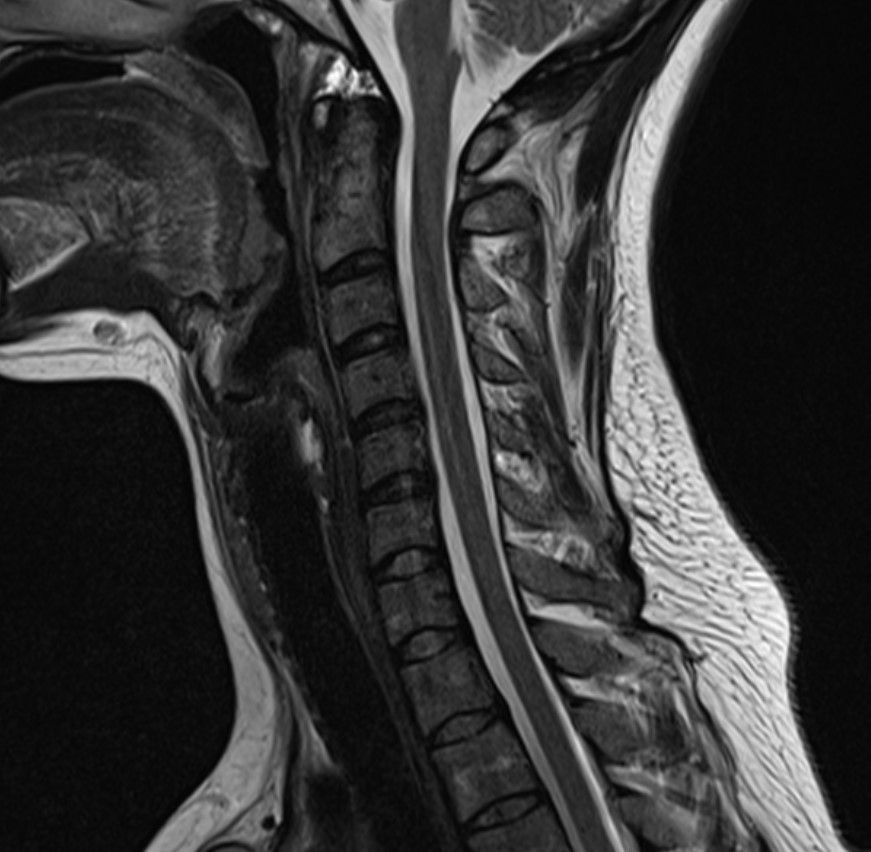

Normal Images Cervical Spine Lateral Xray Cervical Spine CT Cervical Spine MRI Sagittal Cervical Spine MRI Axial Lumbar Spine AP Xray Lumbar Spine Lateral Xray Lumbar Spine CT sagittal Lumbar Spine MRI sagittal Lumbar Spine MRI axial